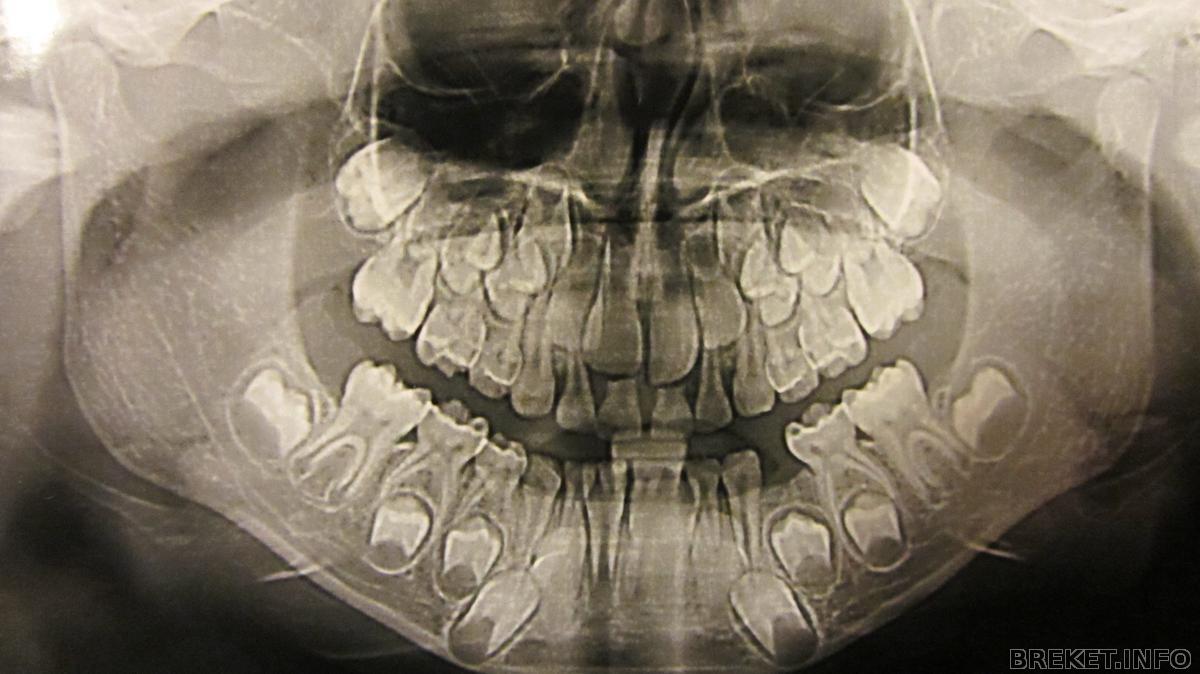

Сама была в шоке!!! детская челюсть

Это снимок моего сыночка . Ему 7 лет . Случайно совершенно заглянула ему в рот

и о Боги !!! Зубик вылез позади центрального резца ( единички )

) Говорит " Рвать , причем сразу два " Ну а что делать , зубы мои ! Мне 30 лет - 4 месяца назад вырвали последний молочный зуб. Воооот ! Сделали снимок . Я его разглядывала и диву давалась

Как однако все хитро устроенно в наших ртах. Зубы вырвали конечно ( это стоило мне игрушечного динозавра и машинки